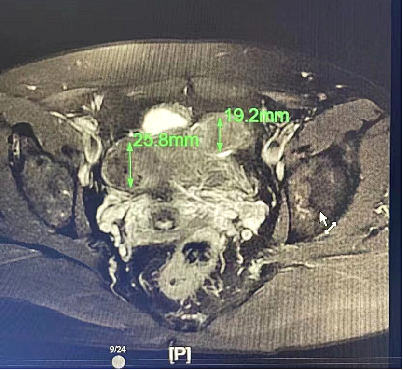

*前                          *后

还能从图像信息中提取出成像区域的温度信号实现对消融手术的实时温度监控这大大提高了*的*性和有效性